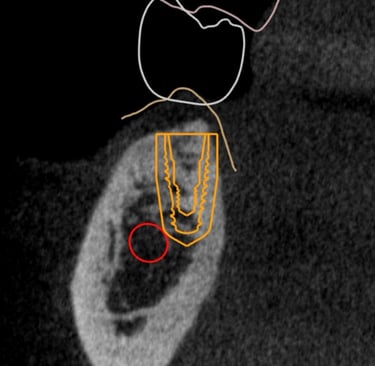

Comparação do Planejamento com o Resultado

Aspecto Tomográfico Final do Enxerto e Planejamento Digital para o Implante

Pouco osso? A cirurgia guiada pode ser a solução.

Mesmo quando há pouca quantidade de osso, muitas vezes não é preciso fazer enxerto.

Com o uso de tecnologia digital em 3D, a cirurgia guiada permite planejar com precisão milimétrica a posição dos implantes, aproveitando ao máximo o osso disponível.

Esse planejamento detalhado também possibilita desviar de estruturas importantes, como o canal mandibular (por onde passa um nervo sensível) e o seio maxilar (uma cavidade natural próxima aos dentes superiores), tornando o procedimento mais seguro e previsível.

O resultado? Cirurgias mais rápidas, com recuperação mais tranquila e excelentes resultados — mesmo em casos que antes pareciam difíceis.

Caso da cirurgia guiada dispensando o enxerto - Imagens originais — nenhuma contém retoques